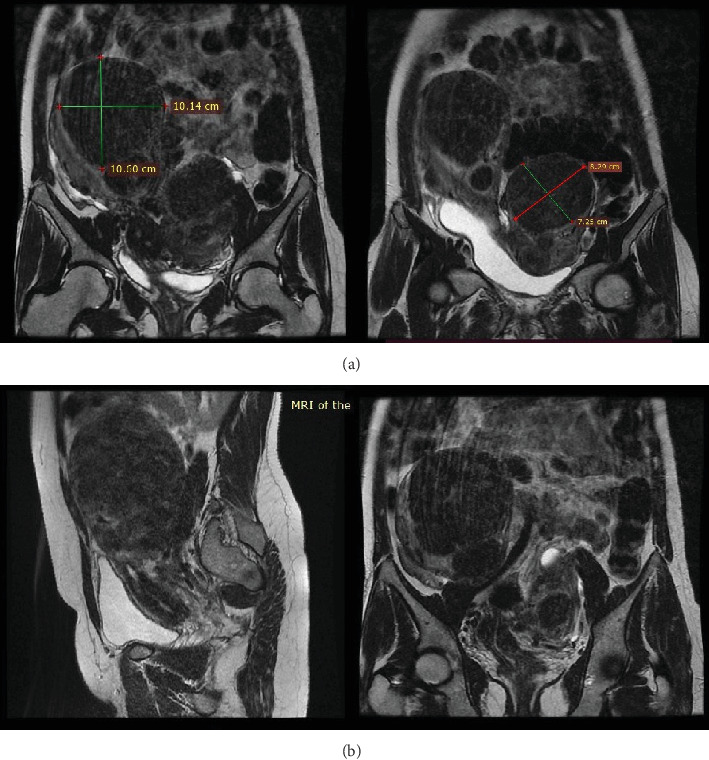

Müllerian duct anomalies and uterine leiomyomas represent distinctive facets of female reproductive health. While uterine leiomyomas are prevalent reproductive pathologies, the coexistence of Müllerian anomalies and leiomyomas is relatively uncommon. This case study examines the complex medical and surgical management of a woman who initially presented with chronic abdominal pain and swelling. Following evaluation, the patient received a diagnosis of an uncommon co-occurrence of congenital uterus didelphys and leiomyomas. Notably, during the surgical procedure, a rectovesical peritoneal band was identified. This case study seeks to broaden the scientific understanding of these subsets of women, offering insights into the complexities arising from a common diagnosis overlaying a rare condition.